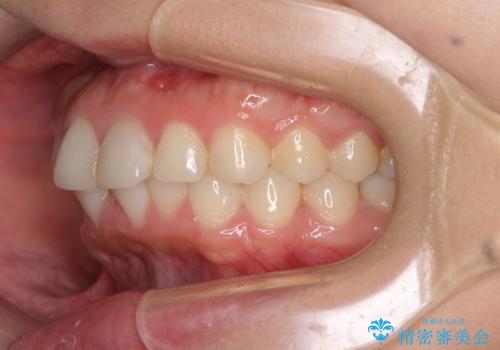

矯正治療の後戻り ガタガタになった前歯の部分矯正

- 以前の矯正治療の後戻りを気にして来院された患者様です。

下顎前歯にデコボコがあるため、ワイヤー矯正により改善することとしました。

もう少しデコボコを改善したかったのですが、ご本人の希望もあり、装置を除去しました。

後戻りを防止するため、舌側を細いワイヤーによる保定を行いました。